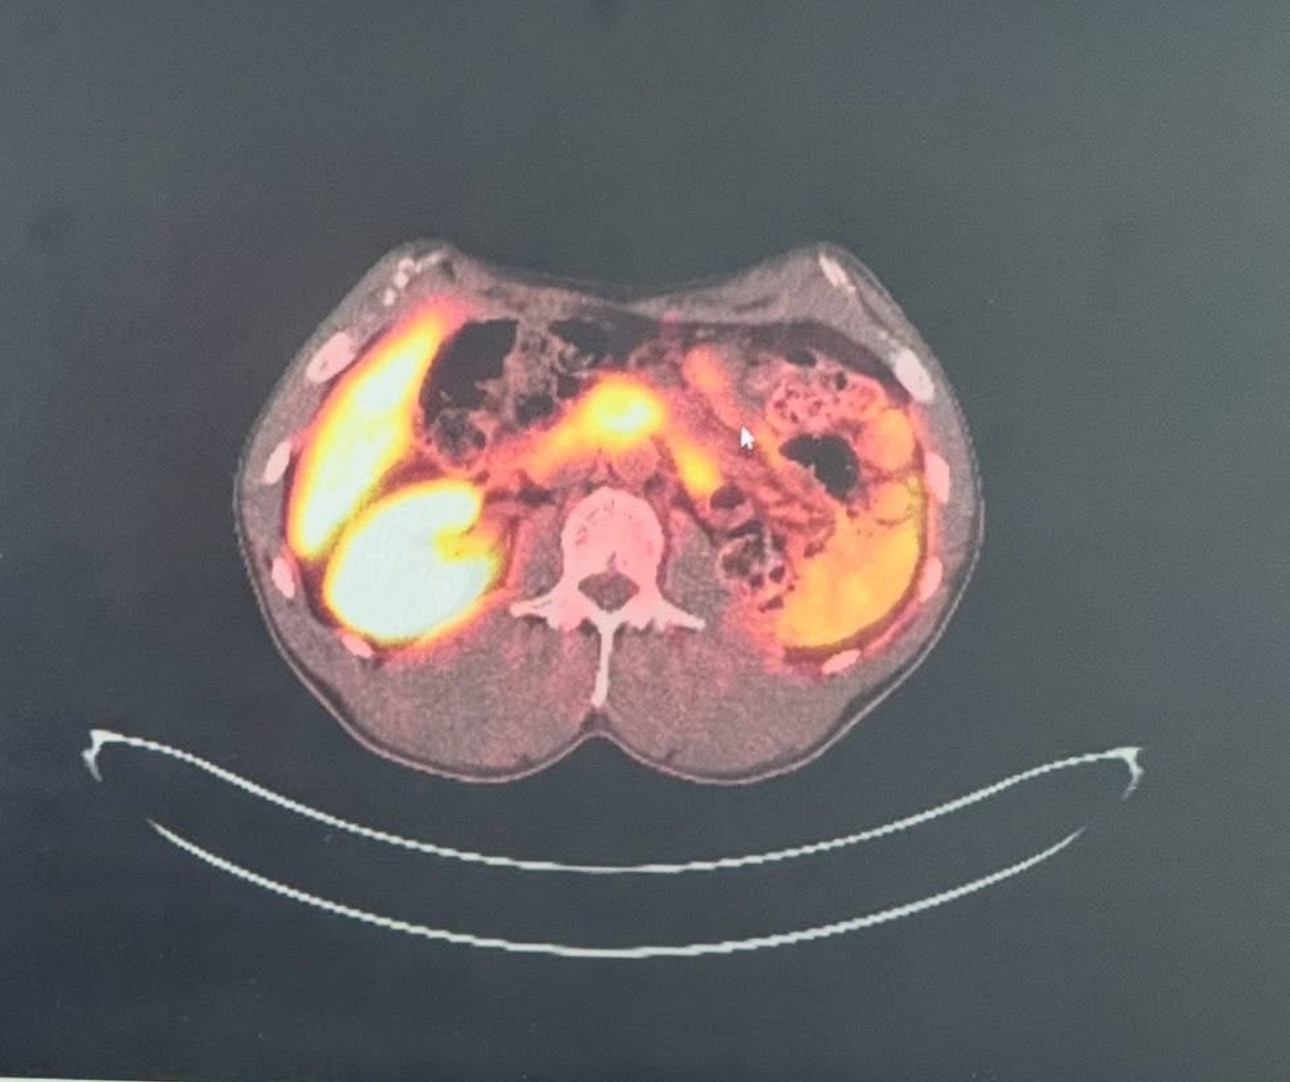

His latest pet scan showed cancer in his kidney, head of the pancreas, both adrenal glands, and his pituitary glands.